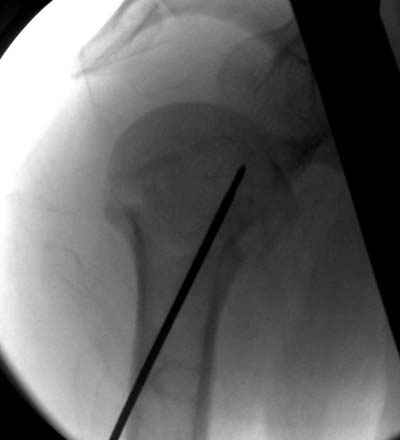

Женя, а как ты водишь спицы, в смысле, как делаешь входное отверстие, и как в него проводишь V-спицу? А то о дна из спиц, та, у которой не дошла до головки одна палочка буквы V, как-то выглядит на рентгенограмме, как будто или через очень большое отверстие введена, или каждая половинка через отдельные отверстия.

В чем ты видишь причину вторичного смещения?

Мне кажется, проблема в том, что не все концы спиц зашли в головку, и зашедшие - недостаточно далеко прошли.

Спицы провожу по передней и задней поверхностям плечевой кости через 4,5 мм отверстия на разных уровнях.

Идеей презентации случая была демонстрация важности постоп Рг - хотя казалось бы все было сделано под флюороскопическим контролем и интраоперационно подозрений на нестабильность не возникло, а такая вот

неожиданность...

Уточни - обе части буквы V вводишь в одно отверстие? А то по снимкам выглядит, что в разные.

V-спица проводится через 4,5 мм отверстие. Видимо, из-за разной длины вторая половина спицы *пролетела* мимо отверстия, что и привело к вторичному смещению костных фрагментов.